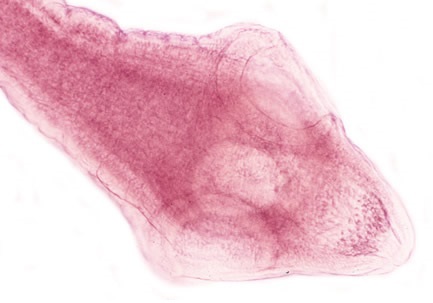

Sán lá ruột lớn (Fasciolopsis buski)

03:15 CH @ 15/07/2016Fasciolopsis buski là loại sán lá lớn, bình thường ký sinh trong tá tràng của heoSán lá Dicrocoelium dendriticum